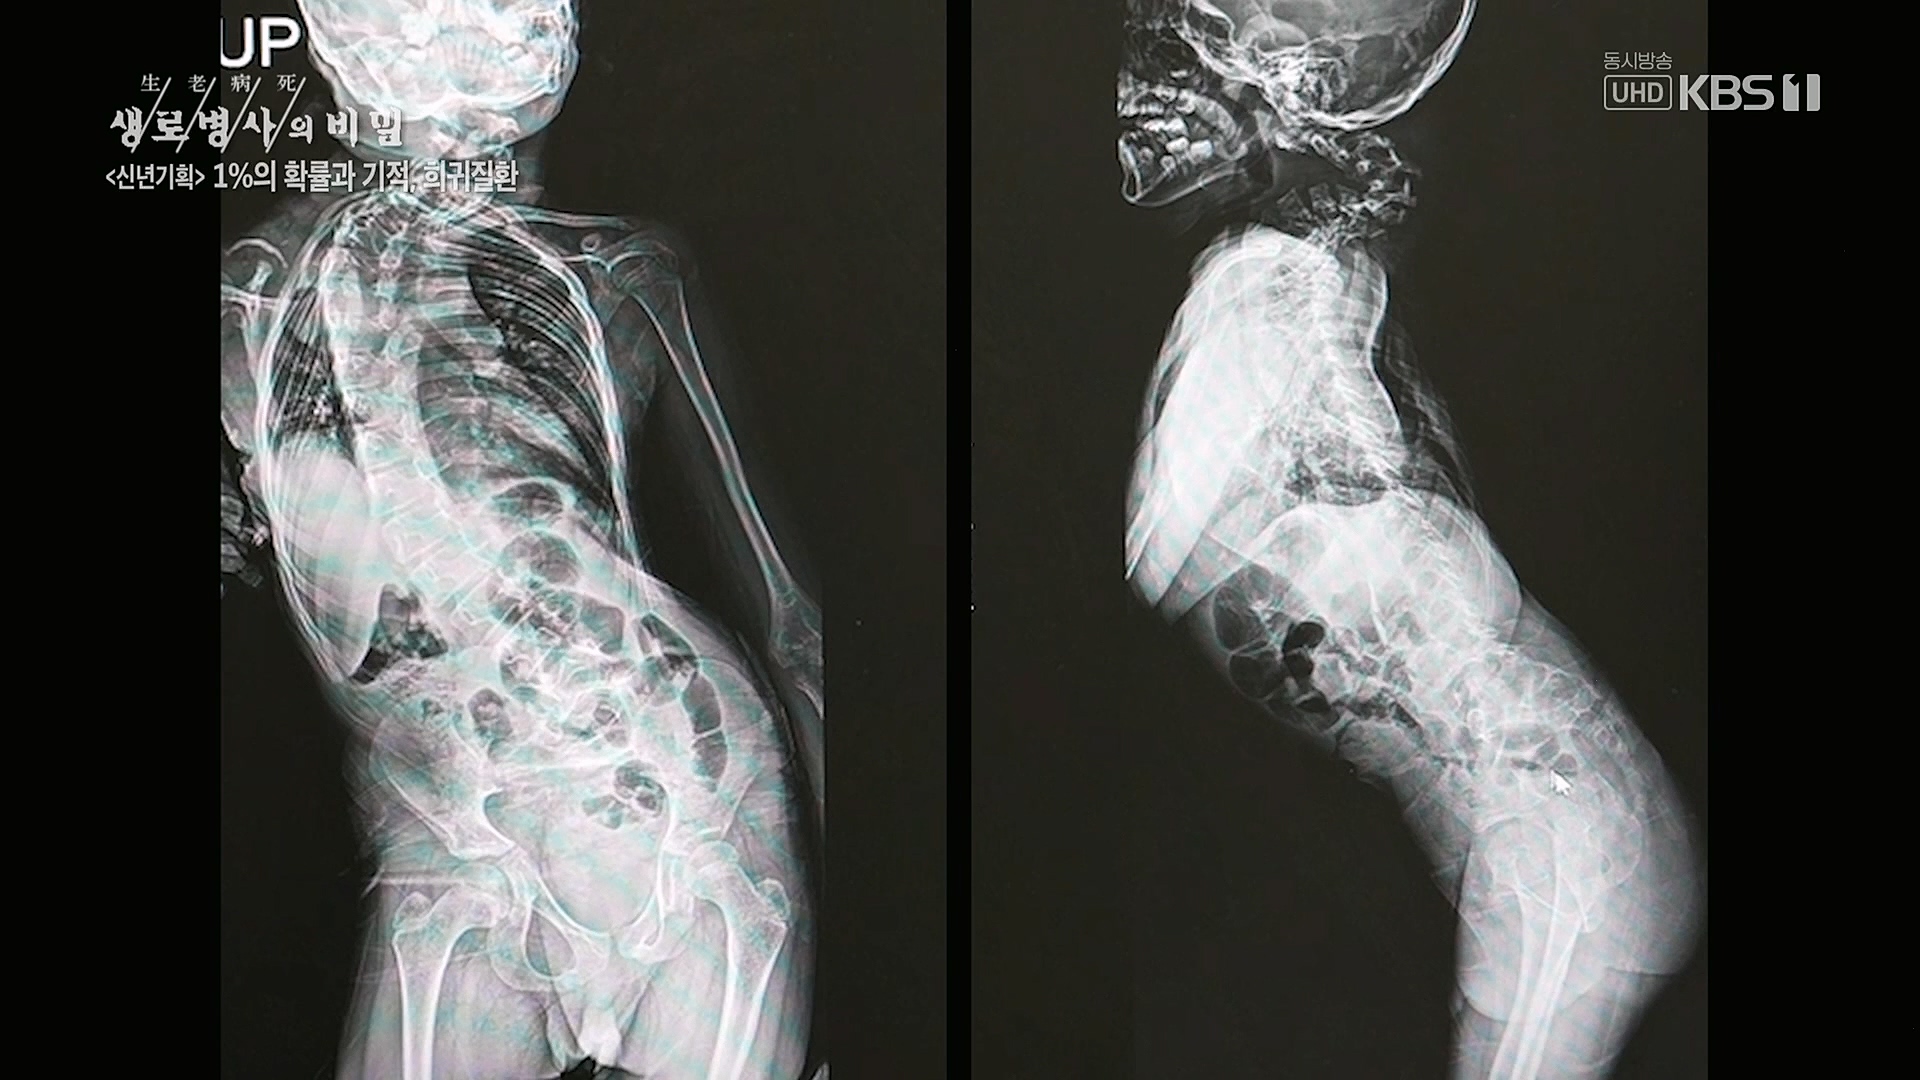

생로병사의 비밀.E850.230104p.H264-F1RST.mp4_20230117_194055.017.jpg 생로병사의 비밀.E850.230104p.H264-F1RST.mp4_20230117_194102.918.jpg 생로병사의 비밀.E850.230104p.H264-F1RST.mp4_20230117_195154.976.jpg 생로병사의 비밀.E850.230104p.H264-F1RST.mp4_20230117_195155.383.jpg 생로병사의 비밀.E850.230104p.H264-F1RST.mp4_20230117_195155.788.jpg 생로병사의 비밀.E850.230104p.H264-F1RST.mp4_20230117_195156.196.jpg 생로병사의 비밀.E850.230104p.H264-F1RST.mp4_20230117_195156.603.jpg 생로병사의 비밀.E850.230104p.H264-F1RST.mp4_20230117_195157.009.jpg 생로병사의 비밀.E850.230104p.H264-F1RST.mp4_20230117_195157.415.jpg 생로병사의 비밀.E850.230104p.H264-F1RST.mp4_20230117_195157.821.jpg 생로병사의 비밀.E850.230104p.H264-F1RST.mp4_20230117_195158.226.jpg 생로병사의 비밀.E850.230104p.H264-F1RST.mp4_20230117_195158.653.jpg 생로병사의 비밀.E850.230104p.H264-F1RST.mp4_20230117_195159.062.jpg 생로병사의 비밀.E850.230104p.H264-F1RST.mp4_20230117_195159.462.jpg 생로병사의 비밀.E850.230104p.H264-F1RST.mp4_20230117_195159.872.jpg 생로병사의 비밀.E850.230104p.H264-F1RST.mp4_20230117_195200.278.jpg 생로병사의 비밀.E850.230104p.H264-F1RST.mp4_20230117_195200.685.jpg 생로병사의 비밀.E850.230104p.H264-F1RST.mp4_20230117_195201.103.jpg 생로병사의 비밀.E850.230104p.H264-F1RST.mp4_20230117_195201.508.jpg 생로병사의 비밀.E850.230104p.H264-F1RST.mp4_20230117_195201.914.jpg 생로병사의 비밀.E850.230104p.H264-F1RST.mp4_20230117_195202.322.jpg 생로병사의 비밀.E850.230104p.H264-F1RST.mp4_20230117_195202.726.jpg 생로병사의 비밀.E850.230104p.H264-F1RST.mp4_20230117_195203.132.jpg 생로병사의 비밀.E850.230104p.H264-F1RST.mp4_20230117_195203.541.jpg 생로병사의 비밀.E850.230104p.H264-F1RST.mp4_20230117_195203.966.jpg 생로병사의 비밀.E850.230104p.H264-F1RST.mp4_20230117_195204.383.jpg 생로병사의 비밀.E850.230104p.H264-F1RST.mp4_20230117_195204.808.jpg 생로병사의 비밀.E850.230104p.H264-F1RST.mp4_20230117_195205.216.jpg 생로병사의 비밀.E850.230104p.H264-F1RST.mp4_20230117_195205.622.jpg 생로병사의 비밀.E850.230104p.H264-F1RST.mp4_20230117_195206.023.jpg 생로병사의 비밀.E850.230104p.H264-F1RST.mp4_20230117_195206.445.jpg 생로병사의 비밀.E850.230104p.H264-F1RST.mp4_20230117_195206.853.jpg 생로병사의 비밀.E850.230104p.H264-F1RST.mp4_20230117_195207.257.jpg 생로병사의 비밀.E850.230104p.H264-F1RST.mp4_20230117_195207.665.jpg 생로병사의 비밀.E850.230104p.H264-F1RST.mp4_20230117_195208.070.jpg 생로병사의 비밀.E850.230104p.H264-F1RST.mp4_20230117_195208.476.jpg 생로병사의 비밀.E850.230104p.H264-F1RST.mp4_20230117_195208.882.jpg 생로병사의 비밀.E850.230104p.H264-F1RST.mp4_20230117_195209.288.jpg 생로병사의 비밀.E850.230104p.H264-F1RST.mp4_20230117_195209.695.jpg 생로병사의 비밀.E850.230104p.H264-F1RST.mp4_20230117_195210.103.jpg 생로병사의 비밀.E850.230104p.H264-F1RST.mp4_20230117_195210.508.jpg 생로병사의 비밀.E850.230104p.H264-F1RST.mp4_20230117_195210.916.jpg 생로병사의 비밀.E850.230104p.H264-F1RST.mp4_20230117_195211.321.jpg 생로병사의 비밀.E850.230104p.H264-F1RST.mp4_20230117_195211.748.jpg 생로병사의 비밀.E850.230104p.H264-F1RST.mp4_20230117_195212.151.jpg 생로병사의 비밀.E850.230104p.H264-F1RST.mp4_20230117_195212.557.jpg 생로병사의 비밀.E850.230104p.H264-F1RST.mp4_20230117_195212.966.jpg 생로병사의 비밀.E850.230104p.H264-F1RST.mp4_20230117_195213.383.jpg 생로병사의 비밀.E850.230104p.H264-F1RST.mp4_20230117_195213.790.jpg